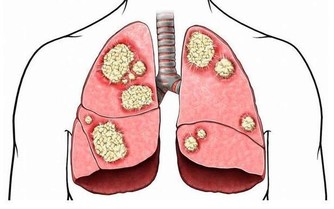

很多人可能會覺得脂肪肝不是啥大事,但事實上,脂肪肝長期不治會導致肝細胞的再生障礙和壞死,進而形成肝纖維化、肝硬化。

要知道,隨著飲酒量的增加,對肝臟的危害是逐步累積的:酒精性脂肪肝→酒精性肝炎→酒精性肝硬化→最後導致肝癌。